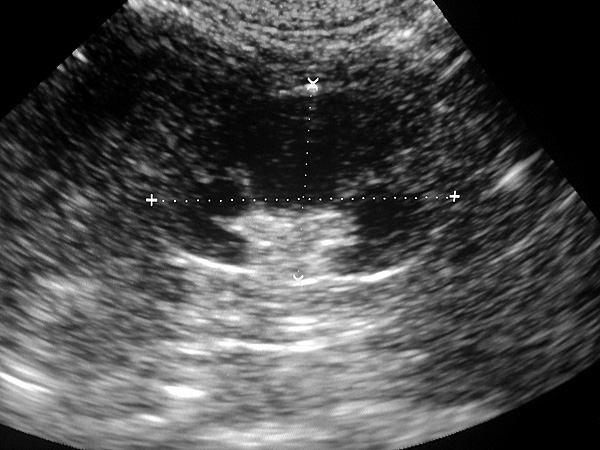

Przykładowy obraz USG

Sonda wytwarza fale ultradźwiękowe. Te przenikają przez poszczególne elementy ciała (nie robiąc przy tym krzywdy badanemu), odbijają się od nich i wracają do sondy. Na ekranie monitora pojawia się więc przetworzone komputerowo echo czyli obraz fal ultradzwiękowych, odbitych od poszczególnych narządów.

Możemy zatem ocenić narządy pod względem ich budowy: wielkości, kształtu, struktury miąższu, zawartości, a także obecności zmian chorobowych: deformacji, obecności płynu, stanu zapalnego itp. To wiedza nieoceniona i czasem bezwzględnie konieczna do postawienia trafnego rozpoznania...